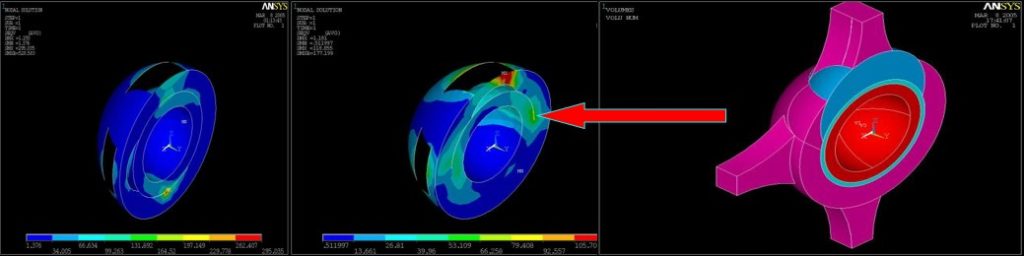

РЕЗУЛЬТАТИ МАТЕМАТИЧНОГО МОДЕЛЮВАННЯ ЗМІН ПРУЖНІХ ДЕФОРМАЦІЙ ПРОТЕЗОВАНОЇ КУЛЬШОВОЇ ЗАПАДИНИ

Найбільш небезпечними для стабільності чашки ендопротеза є дефекти «даху» . Їх присутність приводить до появи зон перевантаження переднього та заднього країв западини, напруження котрих вп’ятеро перевищують межу її міцності – 270 кГ/см2

При наявних дефектах до 50 см3 є можливість досягти первинної фіксації безцементного ендопротеза або надійної первинної фіксації цементного компонента

МОДЕЛЮВАННЯ НАВАНТАЖЕНЬ В ПРОТЕЗОВАНОМУ КОЛІННОМУ СУГЛОБІ